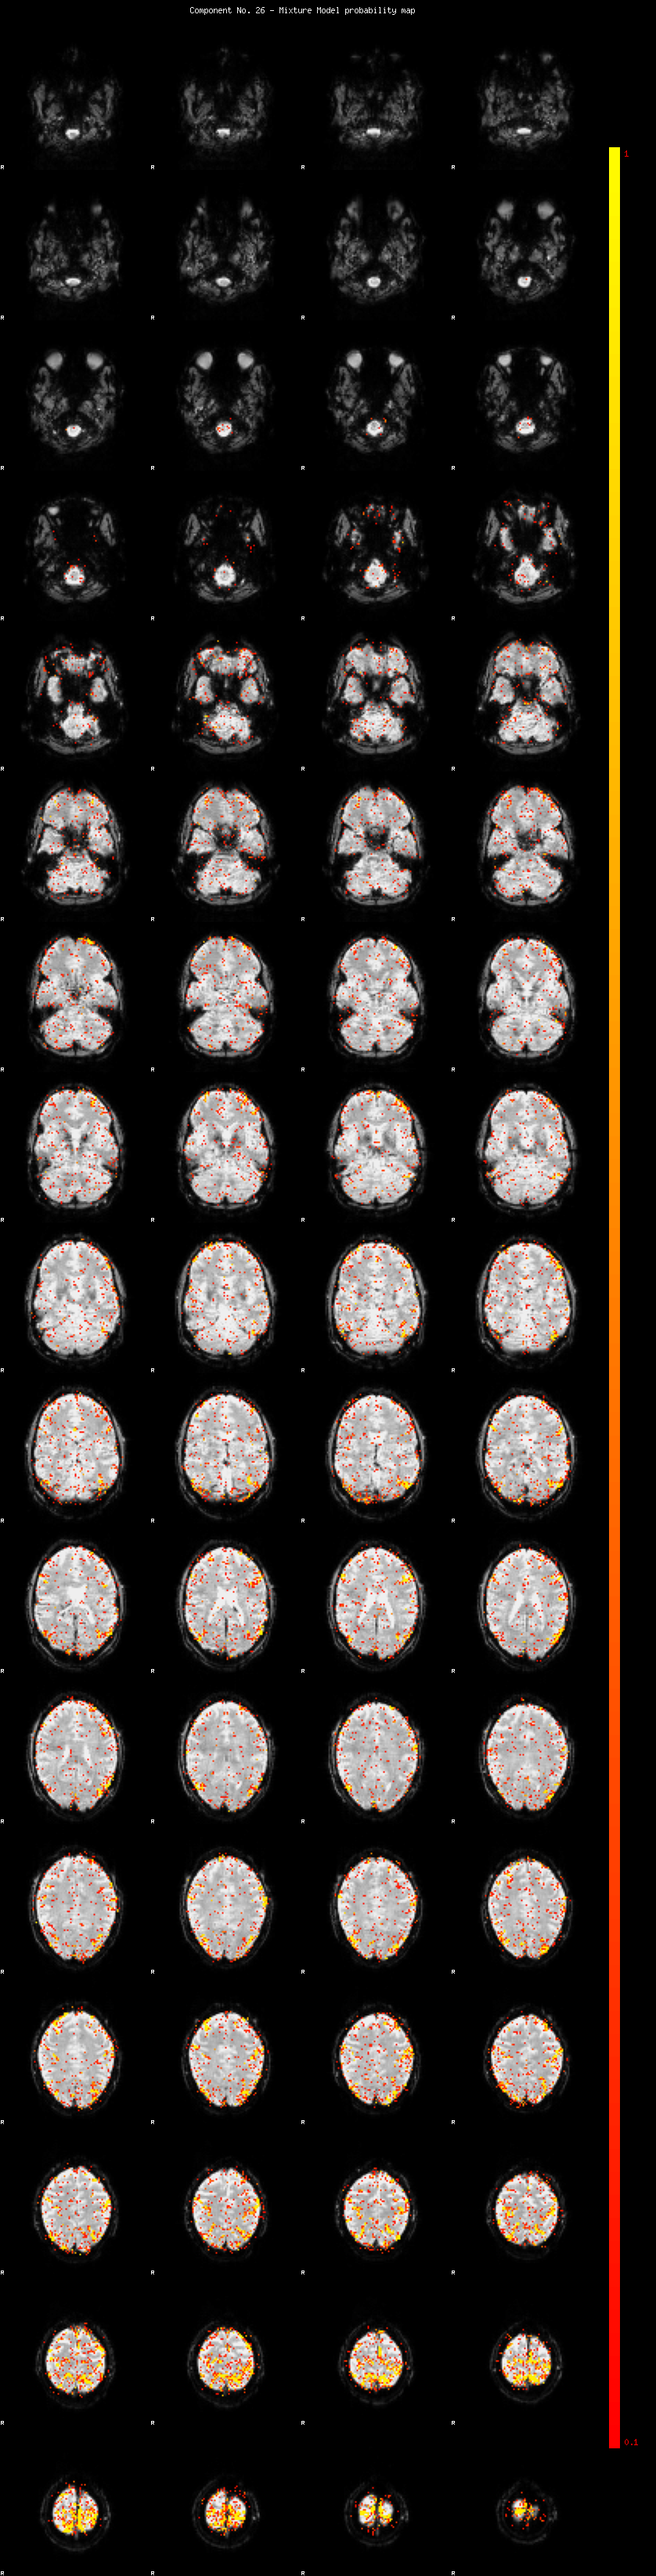

IC_26 Mixture Model fit

Means : 0.000000 3.019549 -2.755741

Vars : 1.000000 3.990694 0.919466

Prop. : 0.951665 0.041341 0.006994